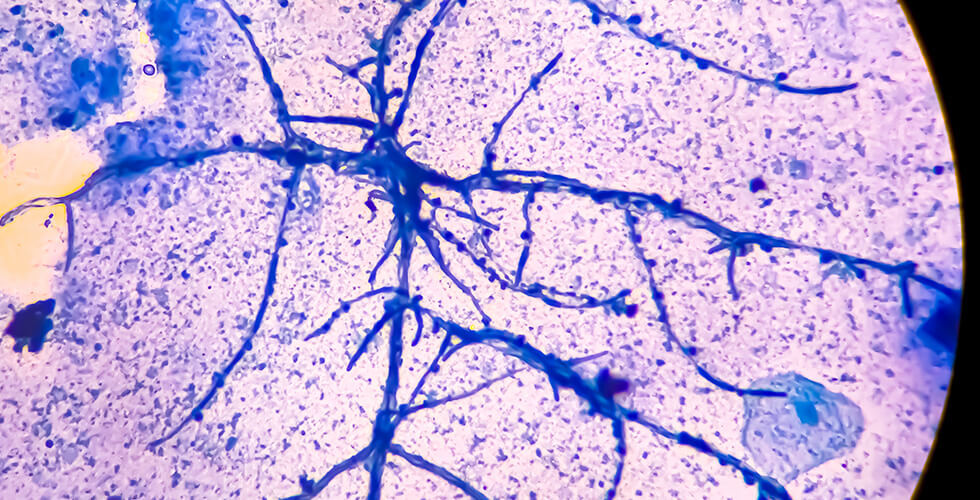

Skin’s Secret Weapon: How a Common Fungus Fights Super-Bug Staph

Did you know your skin is secretly arming you against superbug staph? It turns out that a common skin fungus, Malassezia, quietly manufactures molecules...